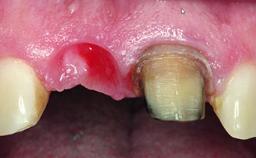

Replacement of a Perforated Upper Left Central Incisor: Early Placement of an RC Bone Level Implant

A 28-year-old patient presented at her general dentist’s office and complained about the appearance of her tooth 21. The patient had a history of trauma to this tooth. Endodontic treatment had been performed in the past and a crown placed on the tooth. A procedure to replace the old crown was performed by her dentist; however, a perforation on the middle third of the root occurred, and extraction of tooth 21 was suggested. Upon clinical and radiographic examination of the patient, who had been referred to us, replacement of tooth 21 by a dental implant appeared to be indicated.